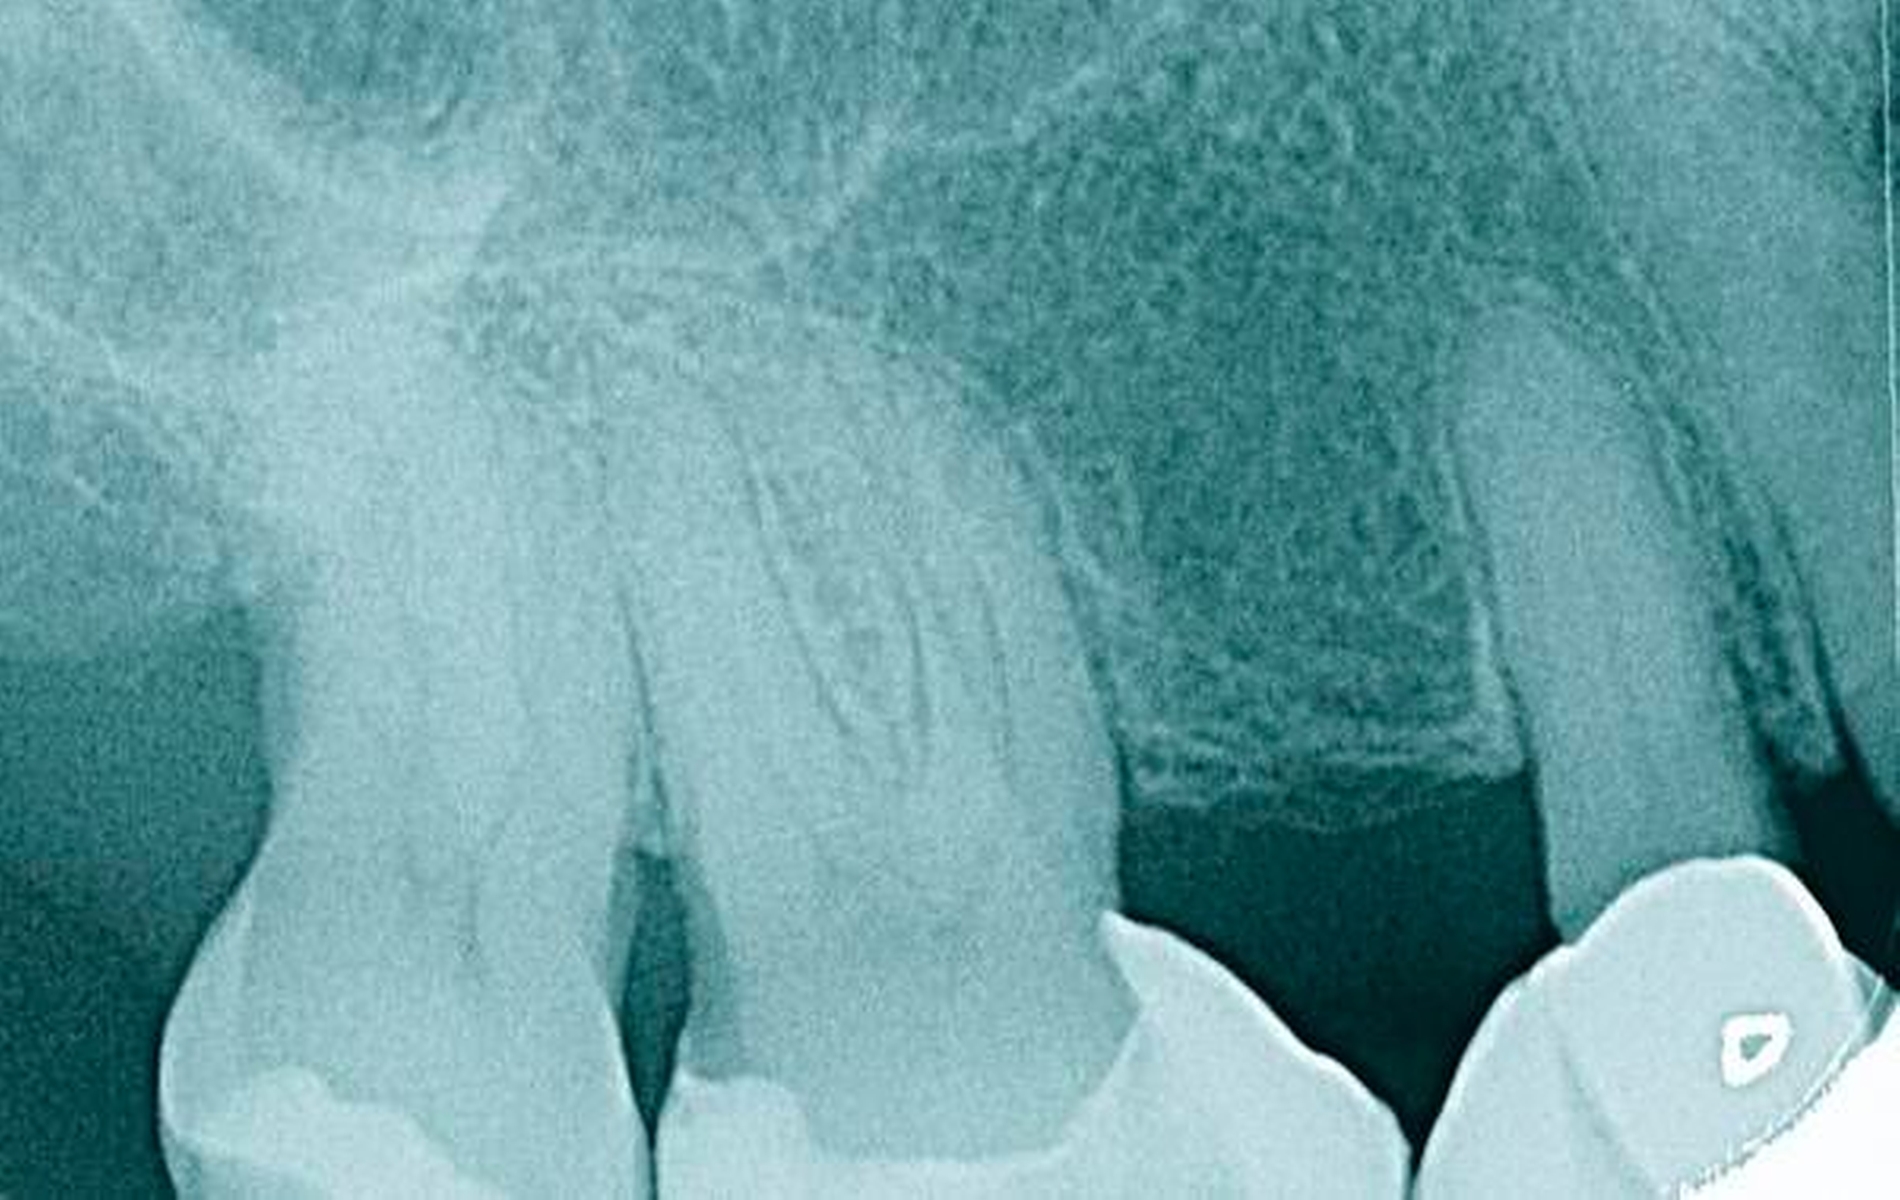

In der Zahnmedizin ist ein Dogma weit verbreitet: „Jede Lücke muss rasch geschlossen werden.“ Tatsächlich gibt es jedoch viele Situationen, in denen es ohne relevante funktionelle und ästhetische Einbußen vertretbar erscheint, eine Lücke zu belassen und regelmäßig zu beobachten (Monitoring). Derzeit erfolgt die Entscheidung „Lücke belassen versus Lücke schließen“ oftmals subjektiv. Sie ist zuweilen weniger von den Patientenvariablen abhängig als von den Schwerpunkten der betreuenden Zahnärzte (Abbildung 4) [Listl et al., 2016]. Ein fachlich fundiertes Vorgehen, das eine Entscheidung unter einer Nutzen-Risiko-Abwägung trifft und ein Monitoring in die Überlegungen einbezieht, kann ebenfalls in die Kategorie der frugalen Interventionen eingeordnet werden. Gleiches gilt für ein Vorgehen im Sinne des Prinzips der verkürzten Zahnreihe, das inzwischen wissenschaftlich gut evaluiert ist [Walter, 2016] und zu dessen Realisierung auch konservierende Maßnahmen beitragen können (Abbildung 5).

Falls ein Lückenschluss nach Gegenüberstellung der Vor- und Nachteile als angemessen angesehen wird, stellt sich die Frage, mit welchen Hilfsmitteln dies erfolgen soll. Derzeit stehen Implantate und klassische Brückenversorgungen im Vordergrund. Es gibt aber auch etliche nicht- oder minimal-invasive Alternativen, die zum Beispiel bei Einzelzahnlücken in Erwägung gezogen werden können. Dazu zählen unter anderem direkte Verfahren wie Zahnverbreiterungen oder -anhänger (Abbildungen 6 und 7) [Staehle, 2009 und 2012; Staehle et al., 2015]. Zurzeit kommen derartige Maßnahmen nur in Einzelfällen in Betracht, es bedarf noch weiterer Evaluationen, um ihr Indikationsspektrum genauer abgrenzen zu können. Es zeichnet sich aber jetzt schon ab, dass sie ein gewisses Potenzial als frugale Interventionen besitzen. Auch wenn momentan vielfach Implantate favorisiert werden, erscheint es dennoch sinnvoll, wenn die Zahnärzteschaft auch diverse Implantat-Alternativen vorhalten kann. Ungeklärte Probleme periimplantärer Entzündungen [Chrcanovic et al., 2016] und die zu erwartende Diskussion über Beziehungen zwischen periimplantären Entzündungen und der Allgemeingesundheit lassen es als sinnvoll erscheinen, solchen Fragen intensiver als bisher nachzugehen. Bislang wird zwar nur über Einflüsse der Allgemeingesundheit auf den Erfolg beziehungsweise Misserfolg von Implantaten diskutiert. Es ist aber nicht auszuschließen, dass man künftig die Fragestellung in umgekehrter Richtung dahingehend erweitert, inwieweit Implantate ihrerseits nicht nur positiven, sondern auch negativen Einfluss auf die Allgemeingesundheit nehmen können.